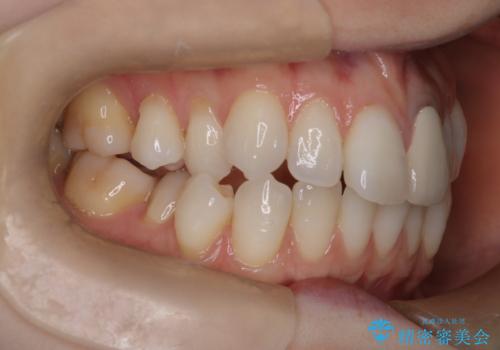

ハーフリンガル矯正|上下4本の抜歯で叢生を改善し、美しい歯並びへ

- 患者様は、歯並びの乱れ(叢生)を整えたいが、前歯の突出感は気にならないとのことで来院されました。診察の結果、全体的な歯列のスペース不足により抜歯が必要と判断。しかし、前歯を大きく下げる必要はなかったため、小臼歯の中でも5番(第二小臼歯)を抜歯する治療計画を立てました。装置は、上顎が舌側(リンガル)、下顎が表側(審美ワイヤー)のハーフリンガル矯正を採用し、目立ちにくさと効率的な歯の移動を両立しました。

抜歯によって歯を並べるためのスペースを確保。その後、ハーフリンガル矯正を用いて、上顎は舌側から、下顎は目立ちにくいワイヤーで歯を誘導し、歯列全体を整えました。治療期間を通じて、噛み合わせのバランスも改善し、機能的にも審美的にも理想的な仕上がりとなりました。患者様からは「目立たずに矯正でき、きれいな歯並びになって嬉しい」とご満足いただきました。